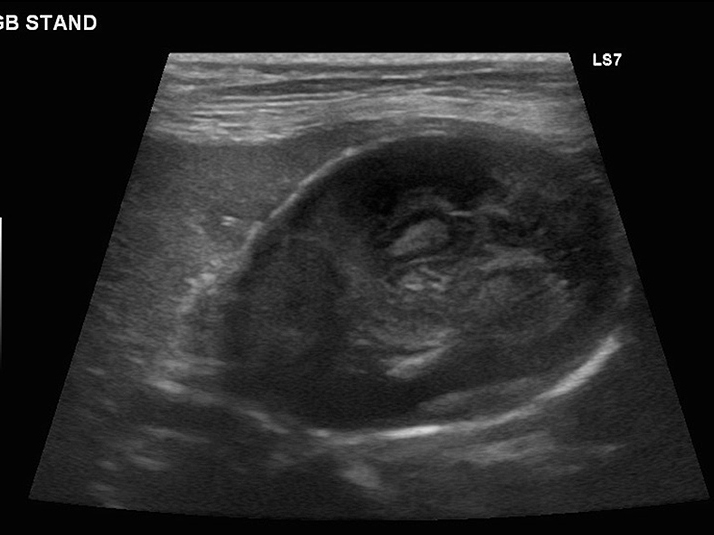

エコー検査では胆嚢の中を満たすほど胆泥が溜まっています。

エコーで胆嚢炎と胆嚢粘液嚢腫であることを確認し、破裂の危険性を考えて腹腔鏡下胆嚢摘出術を実施することになりました。